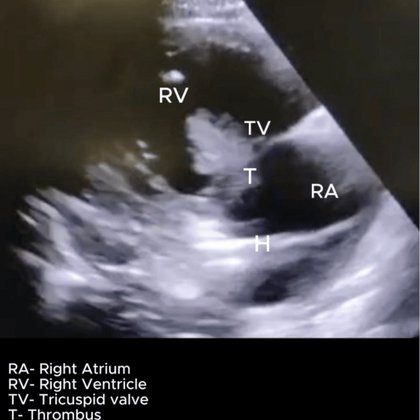

Is that a clot or vegetation? #MedTwitter #Cardiology #echofirst @pocusmeded @WINFOCUS @Echo_Masters @Crit_Care @POCUSJournal @ICS_updates

Pulmonary embolism (PE) represents a significant cause of preventable death among critically ill patients, with the immediate diagnosis impaired by the presence of hemodynamic compromise and lim...